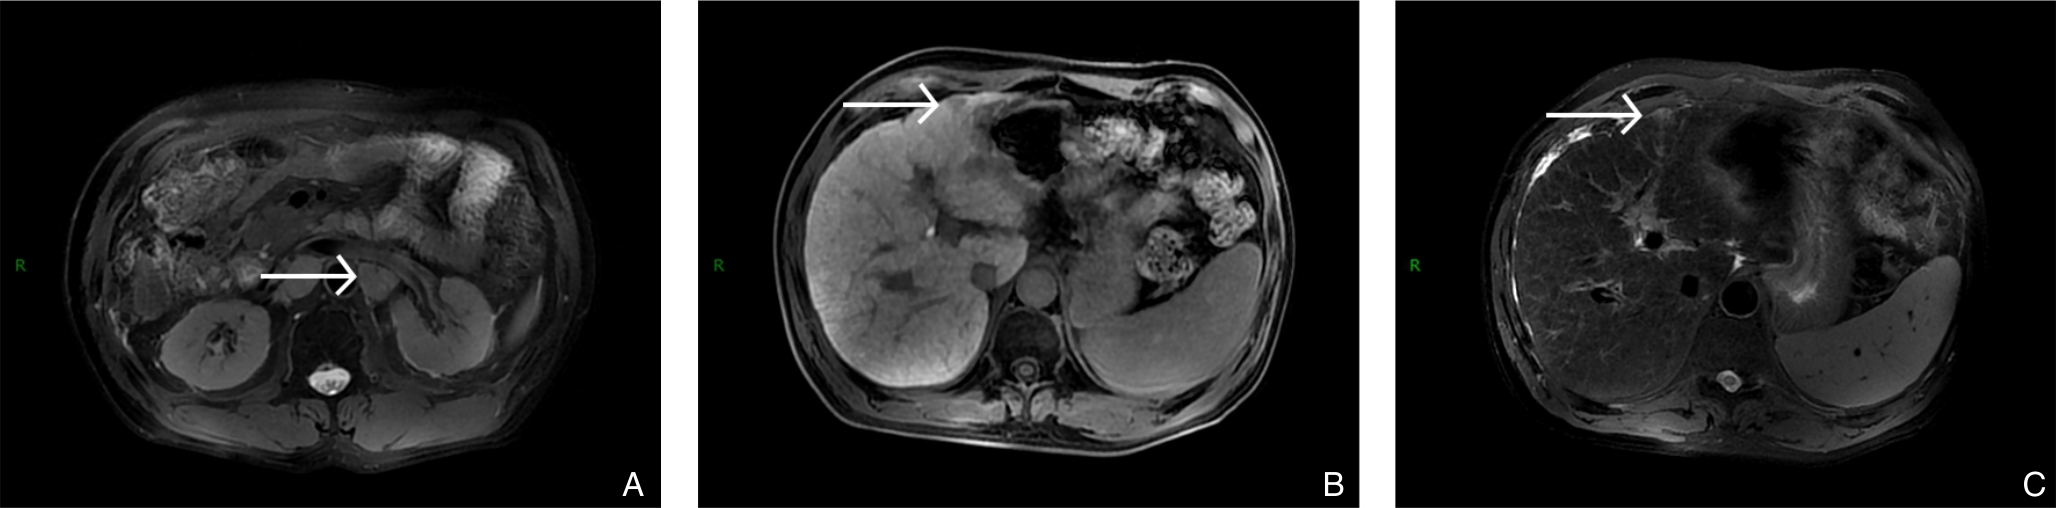

2025, 34(8):1783-1789. doi: 10.7659/j.issn.1005-6947.250076

摘要:背景与目的 肝内胆管癌(ICC)是一种起病隐匿、预后极差、初诊多为进展期的原发性肝癌,其治疗选择有限,预后差。本研究旨在探讨靶向治疗、免疫治疗与肝动脉灌注化疗(HAIC)联合应用于晚期ICC的转化治疗的潜力,为临床转化治疗提供参考。方法 回顾广东医科大学附属医院2021年11月收治的1例晚期ICC行靶向治疗、免疫治疗与HAIC联合治疗后成功转化并接受手术患者的诊治过程,并复习国内外相关文献。结果 患者为52岁男性,确诊为T2N1M0-Ⅲb期ICC。患者拒绝接受以吉西他滨联合顺铂为主的一线化疗方案,同意行靶向治疗联合免疫治疗与HAIC的综合治疗,在接受4个治疗周期后评估肿瘤达到部分缓解,具备实施根治性手术治疗的条件。患者随后接受了腹腔镜下肝S6段和部分S7段切除、胆囊切除以及肝门部和腹膜后淋巴结清扫术。术后患者规律行靶向免疫联合化疗的综合治疗方案。在疾病出现复发和转移后,化疗药物进行了相应调整。截至目前,患者无病生存期达15个月,总生存期超过3年。结论 靶向治疗、免疫治疗与HAIC三联方案可提高晚期ICC患者的转化机会并延长生存期,具有较好的安全性和临床应用前景,但其疗效仍需多中心研究进一步验证。